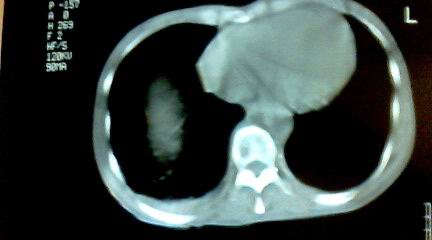

标题: CT25218:请教!胸部CT,胸8椎体骨质破坏,伴周围软组织肿。 [打印本页]

标题: CT25218:请教!胸部CT,胸8椎体骨质破坏,伴周围软组织肿。

患者,女41岁,肢体乏力。

两肺上叶继发性肺结核;胸椎结核并椎旁寒性脓肿形成。

胸椎结核并椎旁寒性脓肿形成。

恶性,椎体淋巴瘤或pnet并肺内转移。